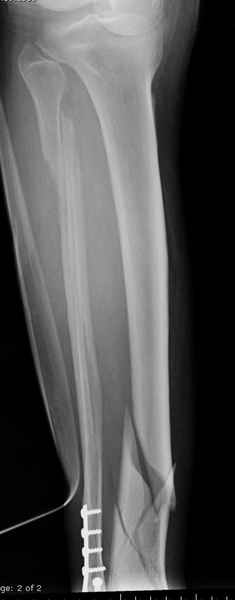

спрашивает что делать с больным который поступил недавно, фермер 55 лет падение при пьяной драке в баре, года два назад перенес операцию на лодыжке, на снимках и КТ перелом без вовлечения сустава,

Повреждение такой локализации, на которой применимы и аппарат (классический Илизарова или гибридный), пластина, особенно Locked Plate, и гвоздь с блокированием. В нашей клинике был бы выполнен закрытый интрамедуллярный остеосинтез. Желательно использовать гвоздь с возможностью провести более чем 2 обычных фронтальных винта в дистальном отломке.

Здесь мы использовали новый Synthes Nail с дополнительными дырками, в проксимальной части 4: по две косых и поперечные (один стандартный а другой динамический), в дистальной части две поперечные, прямая и косая. Вес больного более 120 кг, нагрузку начнем через месяц.

Получилось красиво, поздравляю. Вверху можно было ограничиться одним винтом во фронтальное статическое отверстие, зачем два 45-градусных?

При такий спирали задний край tibia может быть сломан - нет ли этого в данном случае? На всякий случай можно было ввести 1-2 винта 4,5 мм спереди назад мимо гвоздя. Хотя самый дистальный блокирующий винт, возможно, зацепил этот отломок. А какой тут диаметр гвоздя и locking винтов?